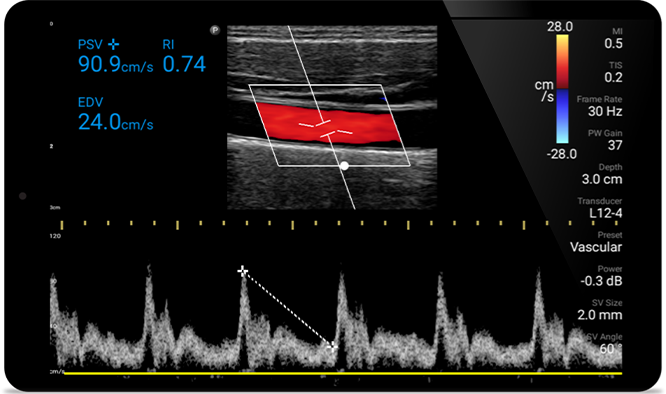

Ecografiile vă pot îmbunătăţi capacitatea de a identifica şi de a trata cu succes abcesele cutanate.

De la dezvăluirea detaliilor fine ale unei imagini până la vizualizarea de înaltă definiție a ţesutului îmbogăţit din mai multe unghiuri, Lumify vă poate ajuta să luaţi decizii în timp real cu mai multă încredere, de la evaluare până la recuperare.